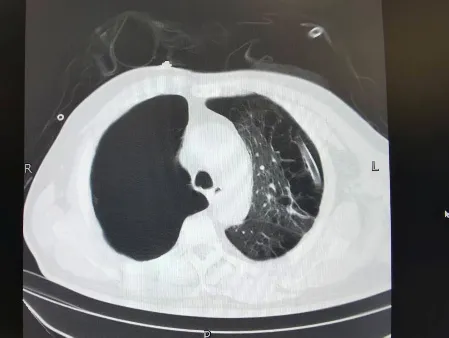

出院前肺CT

术后第三天,在多学科团队的共同照料下,刘先生即可下床活动,胸闷、气短等症状完全消失。复查显示,双侧肺组织复张良好,肺功能指标逐步恢复正常。出院时,普外科、呼吸科与中医团队共同为他制定了长期康复方案,指导他通过戒烟、饮食调理、中药巩固与呼吸训练结合,预防肺部疾病复发。